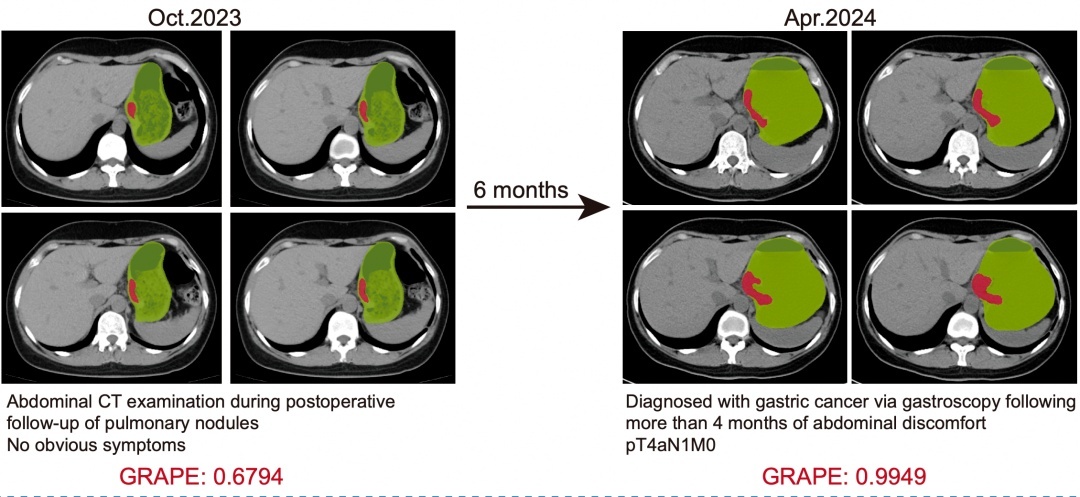

一个令程向东印象深入的案例是,2024年2月,又名45岁的患者因腹部不适,在平阳确诊了T4期胃癌。但团队回溯发现,半年前的2023年10月,这名患者其实为了检讨其他疾病拍过一次平扫CT。

团队将这张旧片子导入AI模子,长短灰的图像上,AI强横地在胃部勾画出一派红色的区域,并给出了68%的胃癌风险警报。

▲AI提前6个月识别出胃癌

这是一份“迟到”的教导。如果其时就有AI模子,就能提前半年确诊。这对又名胃癌患者来说,是极其真贵的生命时间窗。